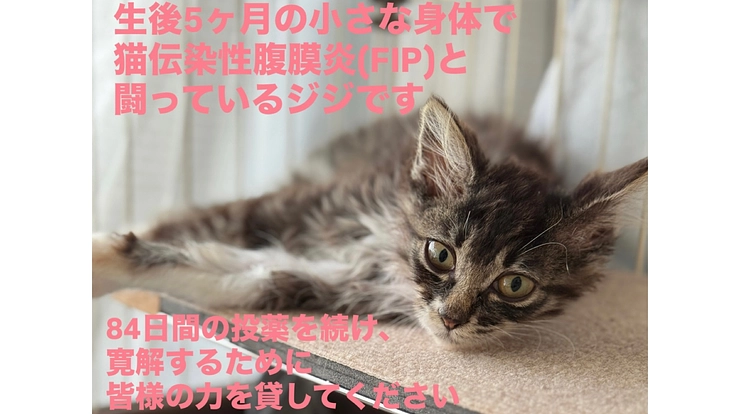

ジジを助けたい‼️‼️‼️

自宅で夫、子ども3人、猫2匹(きなこ4歳、ジジ5ヶ月)

ジジの異変を感じたのは9月12日頃。

元気はあったものの、ご飯を食べる量が減っていきました。

最初は少し食べては休み、また少し食べ、という形で、時間はかかりつつも食べていたのであまり心配はしていませんでした。

9月15日、明らかに食が細くなり、

手であげてもフードを変えても、ふやかしても食べなくなってしまいました。

その頃から食べていないせいで背骨周りはガリガリなのに、お腹だけがふっくらしている…と感じていました。(のちに腹水が溜まっていたと分かりました)

食べられていないので遊ぶ元気もなく、ずっと寝ているようになりました。

ジジがいつも通りご飯を食べてくれるようになってほしい

おもちゃを走って追いかけられるようになってほしい

そんなジジを助けたい一心で、この文章を書いております。

抱っこするとどんどん痩せていくジジを全身で感じるたびに、1日1日命を削りながら必死に生きていることを痛感しています。

自分勝手なお願いなのは重々承知していますが、どうかジジがまた元気に遊び、走り、ご飯が食べられるようになり、この先も猫生を存分に生きられるようにご協力いただけませんでしょうか。